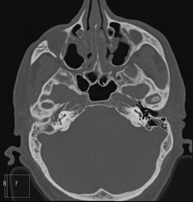

- TC Oídos Prueba radiológica que consiste en obtener imágenes del oído de alta definición anatómica (conducto auditivo interno y externo, tímpano, huesecillos del oído), mediante el empleo de un equipo de TC (Tomografía Computarizada). Indicaciones: trastornos de la audición, cuadros vertiginosos, mareos, acúfenos (pitidos). Prueba radiológica que consiste en obtener imágenes del oído de alta definición anatómica (conducto auditivo interno y externo, tímpano, huesecillos del oído), mediante el empleo de un equipo de TC (Tomografía Computarizada). Indicaciones: trastornos de la audición, cuadros vertiginosos, mareos, acúfenos (pitidos).

- TC Peñascos Prueba radiológica que consiste en obtener imágenes del hueso peñasco del temporal (oído interno, medio y externo) de alta definición anatómica mediante el empleo de un equipo de TC (Tomografía Computarizada). Indicaciones: pérdida de audición súbita o crónica, cuadros vertiginosos, mareo, malformaciones congénitas. Prueba radiológica que consiste en obtener imágenes del hueso peñasco del temporal (oído interno, medio y externo) de alta definición anatómica mediante el empleo de un equipo de TC (Tomografía Computarizada). Indicaciones: pérdida de audición súbita o crónica, cuadros vertiginosos, mareo, malformaciones congénitas.